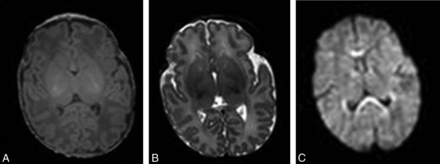

MR imaging is an ideal diagnostic technique for the evaluation of infants and fetuses1⇓⇓⇓⇓⇓–7 because of the absence of ionizing radiation, the superior contrast of soft tissues compared with sonography, and the availability of different contrast options (T1-weighted, T2-weighted, and diffusion-weighted imaging, Fig 1) to improve characterization of both anatomy and pathology. However MR imaging remains a relatively slow technique, with scanning times for most applications in the order of seconds to minutes, leaving them susceptible to motion artifacts. The normally mobile fetus and the unsettled neonate present a major difficulty because the presence of motion during a long acquisition will decrease image quality in the form of motion artifacts (Fig 2), hamper accurate image interpretation, and often necessitate a repeat MR imaging to establish a diagnosis. This may have major emotional implications for parents and can stress the tight budgets of health care providers.

T1-weighted (A), T2-weighted (B), and diffusion-weighted (C) axial MR brain images of a 5-day-old full-term neonate without motion artifacts acquired at 1.5T.

T1-weighted (A), T2-weighted (B), and diffusion-weighted (C) axial MR brain images of a 14-day-old full-term neonate acquired at 1.5T. Motion artifacts in the form of high-signal-intensity ghosts can be seen.